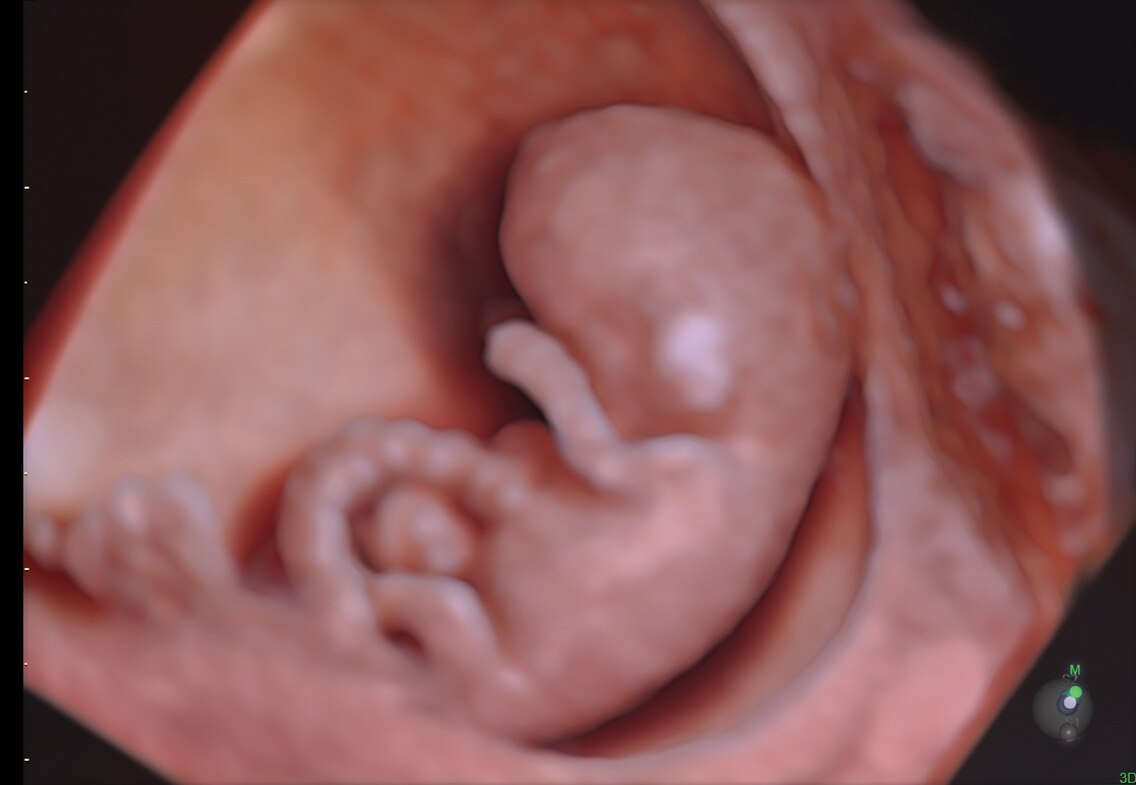

HDlive

Obtenha facilmente imagens de volume com profundidade e clareza sem precedentes usando o conjunto de tecnologia HDlive™, uma ferramenta essencial para a solução de problemas.